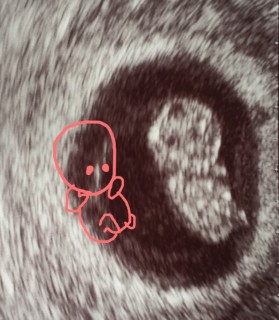

前回の検診が6週でわずか5mmしかなかった胎芽が、今や25.4mmの人の形をした胎児になっていて、すごく感動しました。先生に座ってるねーと言われて、よく見ると体育座り?で凄く可愛くて1人で萌えてました笑